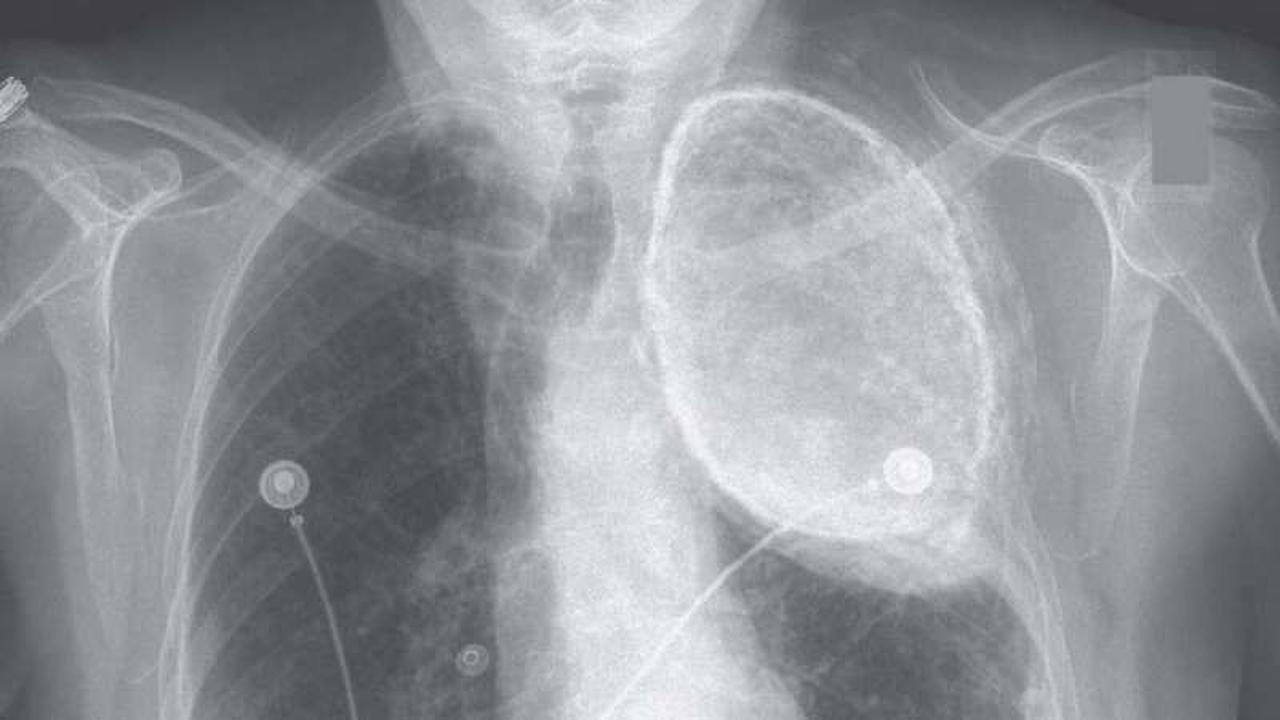

Dari hasil rontgen, terlihat sesuatu yang menghitam di daerah atas paru-paru kirinya. Usut punya usut, ternyata wanita itu pernah menerima pengobatan yang dikenal sebagai oleothorax pada 1950 untuk mengobati tuberkolusis.

Pengobatan kuno tersebut dilakukan dengan menyuntikkan minyak ke dalam pleura (ruang tipis di antara paru-paru). Selama beberapa dekade, pengobatan ilegal itu lazim dipraktekkan di dunia Barat. Minyak yang digunakan pun bervariasi, seperti minyak zaitun, minyak ikan cod, minyak kacang, minyak biji kapas, atau bahkan parafin cair.

"Sayangnya, kita tak bisa mengatakan apa jenis minyak itu hanya dengan melihat hasil rontgen," ujar Abhilash Koratala, asisten profesor kedokteran yang menyelidiki kasus ini.